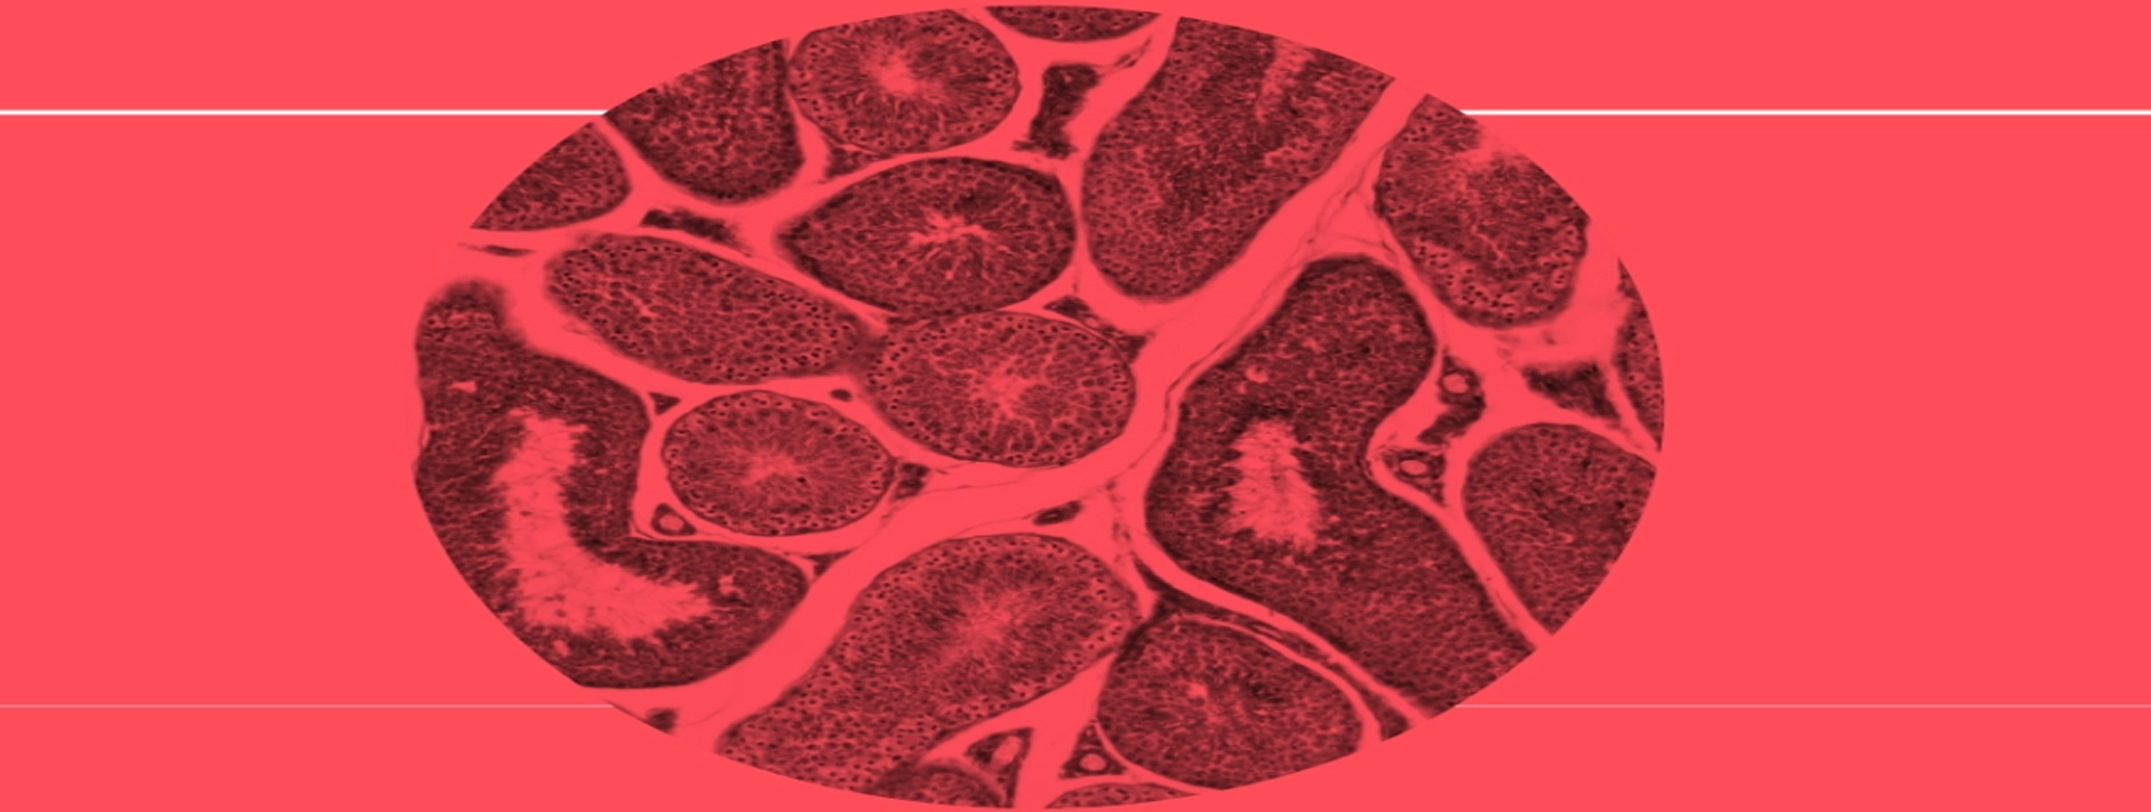

Systemic Sclerosis